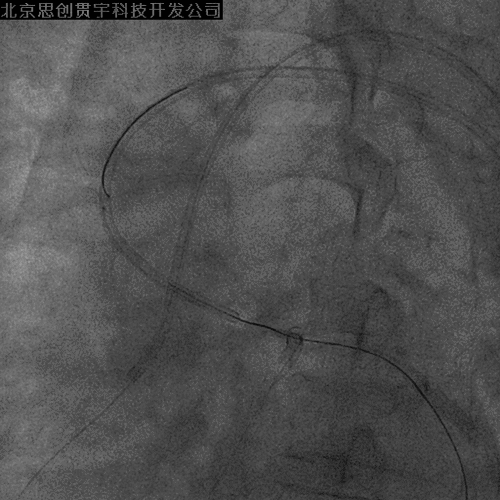

7F XB3.5指引; Pilot 150导丝;Finecross 130cm MG

LAD-IVUS

LAD中段既往支架膨胀不良

导丝主要位于真腔

LCX-正向导丝无法通过病变

IVUS引导反复尝试

Finecross+Pilot 200等

20min后仍无法通过

拟采用逆向技术